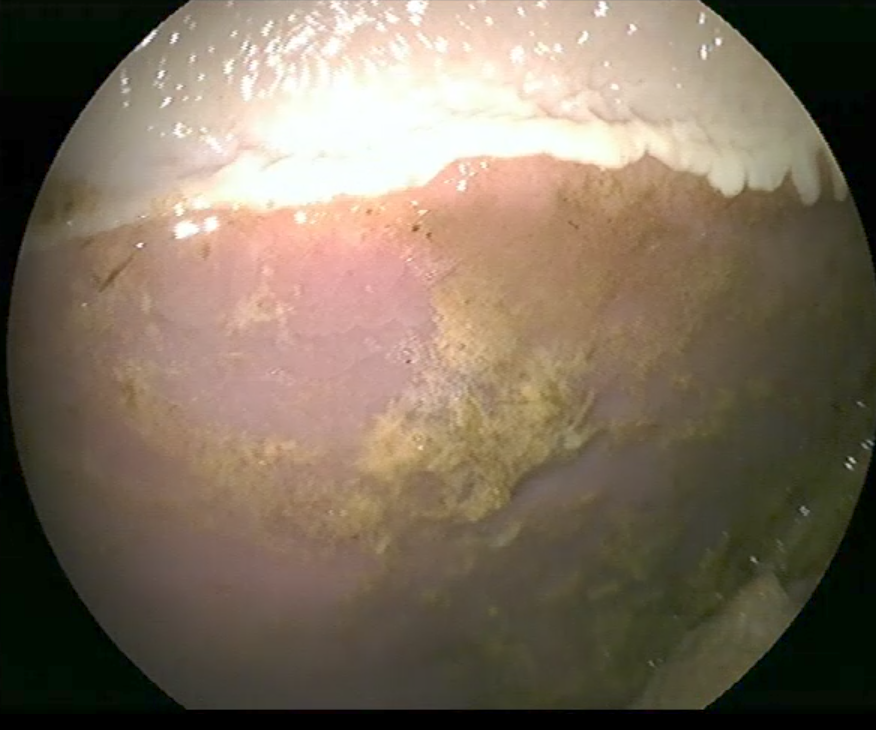

| • | Um den Stress bei der Gastroskopie zu minimieren und das Einbringen des Gastroskops zu erleichtern ist eine leichte Sedierung für die Untersuchung notwendig. Nach der Sedierung wird ein langer, flexibler Schlauch, der eine Optik trägt, durch die Nüster des Pferdes eingeführt und vorsichtig durch die Speiseröhre in den Magen vorgeschoben. Dabei werden Speiseröhre und Magen beurteilt. Nur bei einem nahezu vollständig leeren Magen ist eine genaue Untersuchung der Magenwände, der Schleimhaut und des Magenein- und ausgangs möglich. |

Besondere Aufmerksamkeit gilt auffälligen Bereichen, wie Rötungen, Blutungen oder Geschwüren. Es können darüber hinaus auch andere Probleme wie Magenentleerungsstörungen oder Parasitenbefall (z. B. Magendasseln) diagnostiziert werden. Falls notwendig, können während der Gastroskopie Proben entnommen und Fotos und Videos zur weiteren Auswertung angefertigt werden.